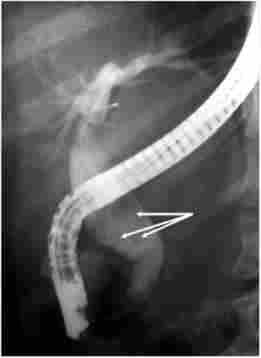

Крім огляду БДС може бути виконана ендоскопічна ретроградна холангіопанкреатографія (ЕРХПГ), яка в значній мірі (до 98-100%) розширює відомості про патологію жовчовивідних шляхів (рис. 18.2). ЕРХПГ проводиться шляхом кашолірованія БДС під контролем дуоденоскопа з подальшим введенням в жовчні протоки контрастної речовини і виконанням рентгенівського дослідження. При необхідності діагностичний етап дослідження може перейти в лікувальний - розсічення іапілли з метою створення вільного відтоку жовчі в кишку (ендоскопічна папиллосфинктеротомия - ЕПСТ), видалення каменів з жовчних проток (літоекстракція), постановка дренажної трубки в жовчний протік з виведенням її через ніздрю (назобі - ліарное дренірваніе).

Ендоскопічна ретроградна холангіопанкреатографія. Камені в розширеному холедохе (вказані стрілками)

Мал. 18.2. Ендоскопічна ретроградна холангіопанкреатографія. Камені в розширеному холедохе (вказані стрілками)